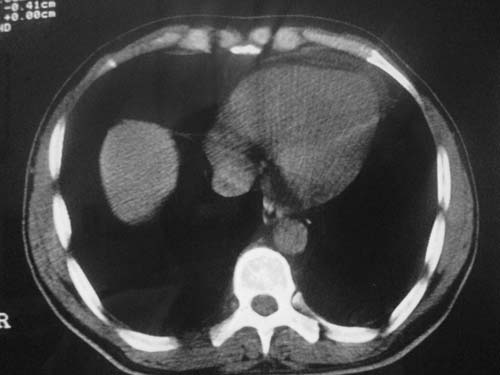

男性39岁,干咳一个月,最近胸憋气短,自己感觉发烧出汗,要求拍ct

图像质量较差请多包含,考虑肺癌,肺结核不除外,大家是否同意这种看法,请各位老师指教

左肺上叶中央型肺癌并阻塞性肺不张。

考虑:左肺上叶中央型肺癌并阻塞性肺不张。左肺下叶囊肿或支扩。

1.左侧肺癌伴阻塞性肺炎,纵隔转移。2.左下肺大泡。3.左下肺感染

纵隔淋吧结肿大

心包积液

双侧胸膜增厚

左肺上叶中央型肺癌并阻塞性肺不张。左下转移,支扩!

左肺上叶中央型肺癌并阻塞性肺不张,纵隔淋巴结转移。